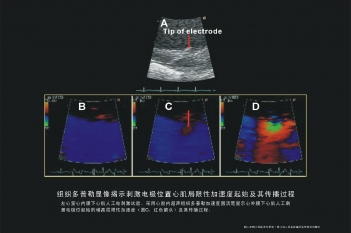

电极位置心肌局限性加速